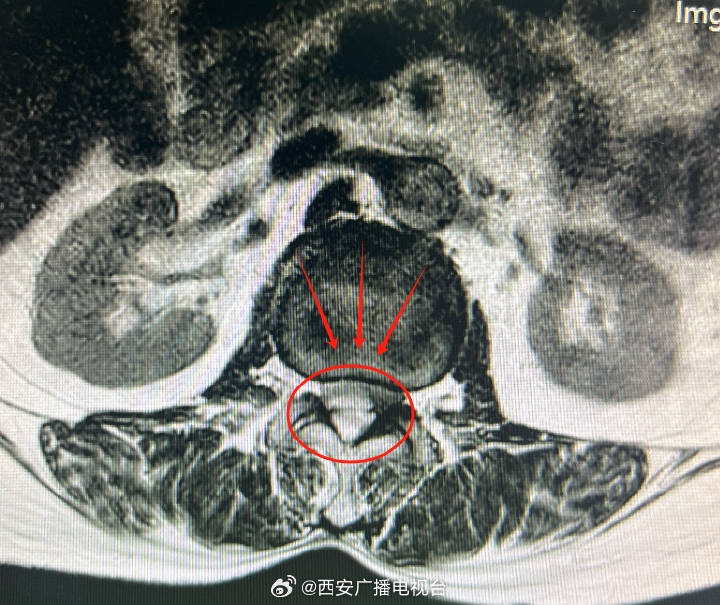

“从赵阿姨的影像资料来看,确实看到腰4-5有个轻微滑脱。”杨俊松表示“但还需要结合症状等才能给出准确诊断!”结合患者的病史、症状、体征和影像资料分析后,杨俊松认为,赵阿姨虽然影像上有腰椎滑脱但症状却与影像并不符合,没有出现坐骨神经痛症状,而是出现骨神经压迫症状——大腿前侧疼痛。症状和影像不符,结合赵阿姨长期高血压史和长期服用利血平史,高度怀疑为自发性硬膜外血肿。

自发性硬膜外血肿治疗主要是血肿清除,以避免神经功能损伤加重。传统手术方式需要内固定维持腰椎生物力学稳定,但赵阿姨还有骨质疏松,钉棒固定系统容易松动。杨俊松根据赵阿姨的病情制定内镜下单侧椎板入路双侧椎管减压手术(ULBD)的方案。

“内镜下ULBD同样可以完成血肿清除!”杨俊松表示,“更重要的是以只需要一个不到1厘米切口微创手术就能达到和传统手术同样的治疗效果!”在将赵阿姨血压控制到合适范围后,杨俊松紧急完成手术。